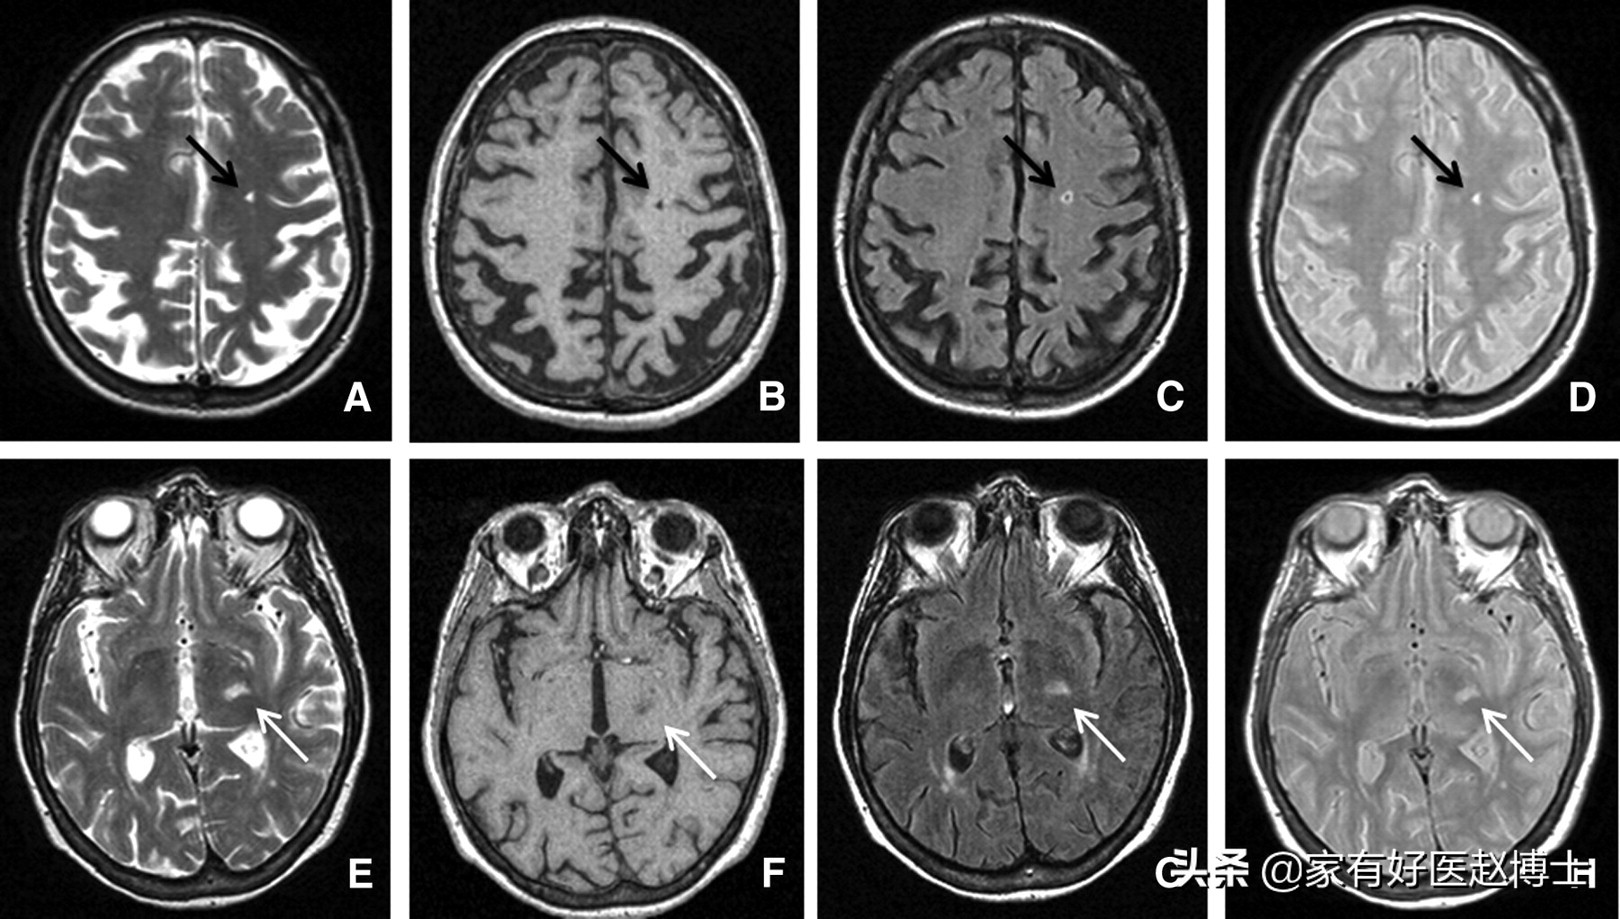

第五个要说的是“腔隙性脑梗塞”,这在颅脑CT或磁共振检查当中是中老年朋友们比较常见的一种异常结果。

腔隙性脑梗塞不同于大面积脑梗塞,很多时候医生并不会给与特殊的治疗意见。但是,腔隙性脑梗塞被认为与大脑里小动脉的内皮功能障碍密切相关,因此,也属于血管老化的一种表现。